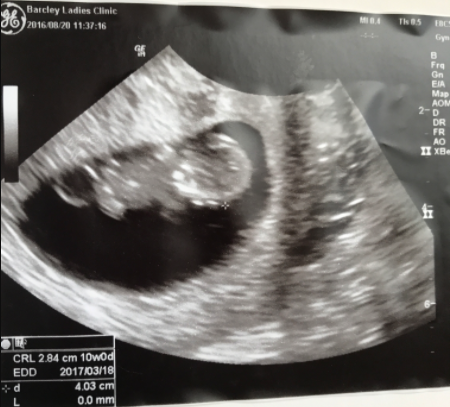

16週0日(16w0d・男の子)|ゆきあママ さん(20歳)

エコー写真撮影時のエピソード:

中々婦人科に行けなくて久しぶりに行った時に徐々に人間らしくなってきて本当にうれしかったです!

前に辛い思いをしてたのですくすくお腹の中で成長して行ってくれてることが何よりも安心でした 旦那も喜んでました。